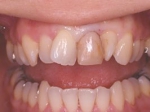

インセラム(オールセラミック)症例②

治療前治療前術前 治療後治療後術後 歯の尖端の透明感までよく再現できている。